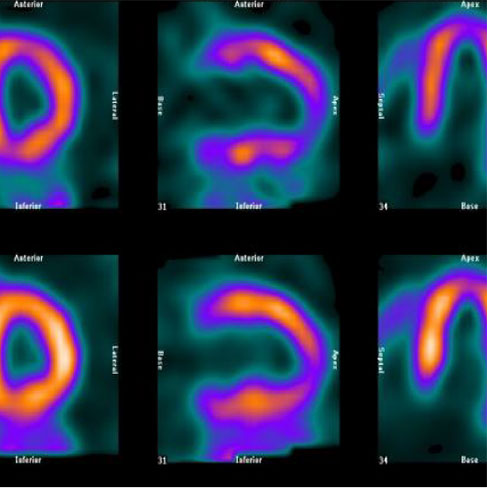

A Cardiac PET scan is noninvasive imaging of the heart by injecting a radiotracer into the peripheral vein. A cardiac PET scan is useful for the assessment of viable myocardium in ischemic cardiomyopathy which guides interventional and/or surgical coronary revascularization procedures. There is a unique role of PET/CT imaging for the detection of cardiac infection/inflammation e.g. sarcoid involvement and the monitoring of its response to appropriate immunosuppressive treatment.

• MYOCARDIAL VIABILITY

• INFECTION (SARCOIDOSIS)

(Rest MPI + 18F-FDG Cardiac PET)